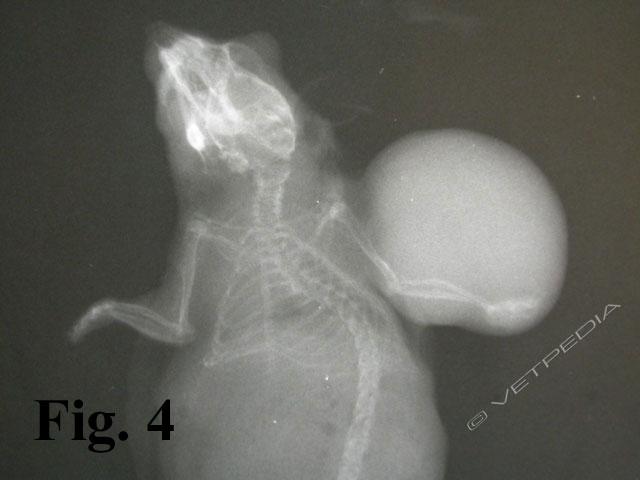

L’esame radiografico di norma si può eseguire senza sedazione; si può eventualmente eseguire una breve anestesia gassosa con induzione diretta. Viste le dimensioni della cavia, conviene eseguire di routine le proiezioni laterale e ventrodorsale di tutto il corpo, a meno che l’animale non sia gravemente debilitato e manovre stressanti poss...